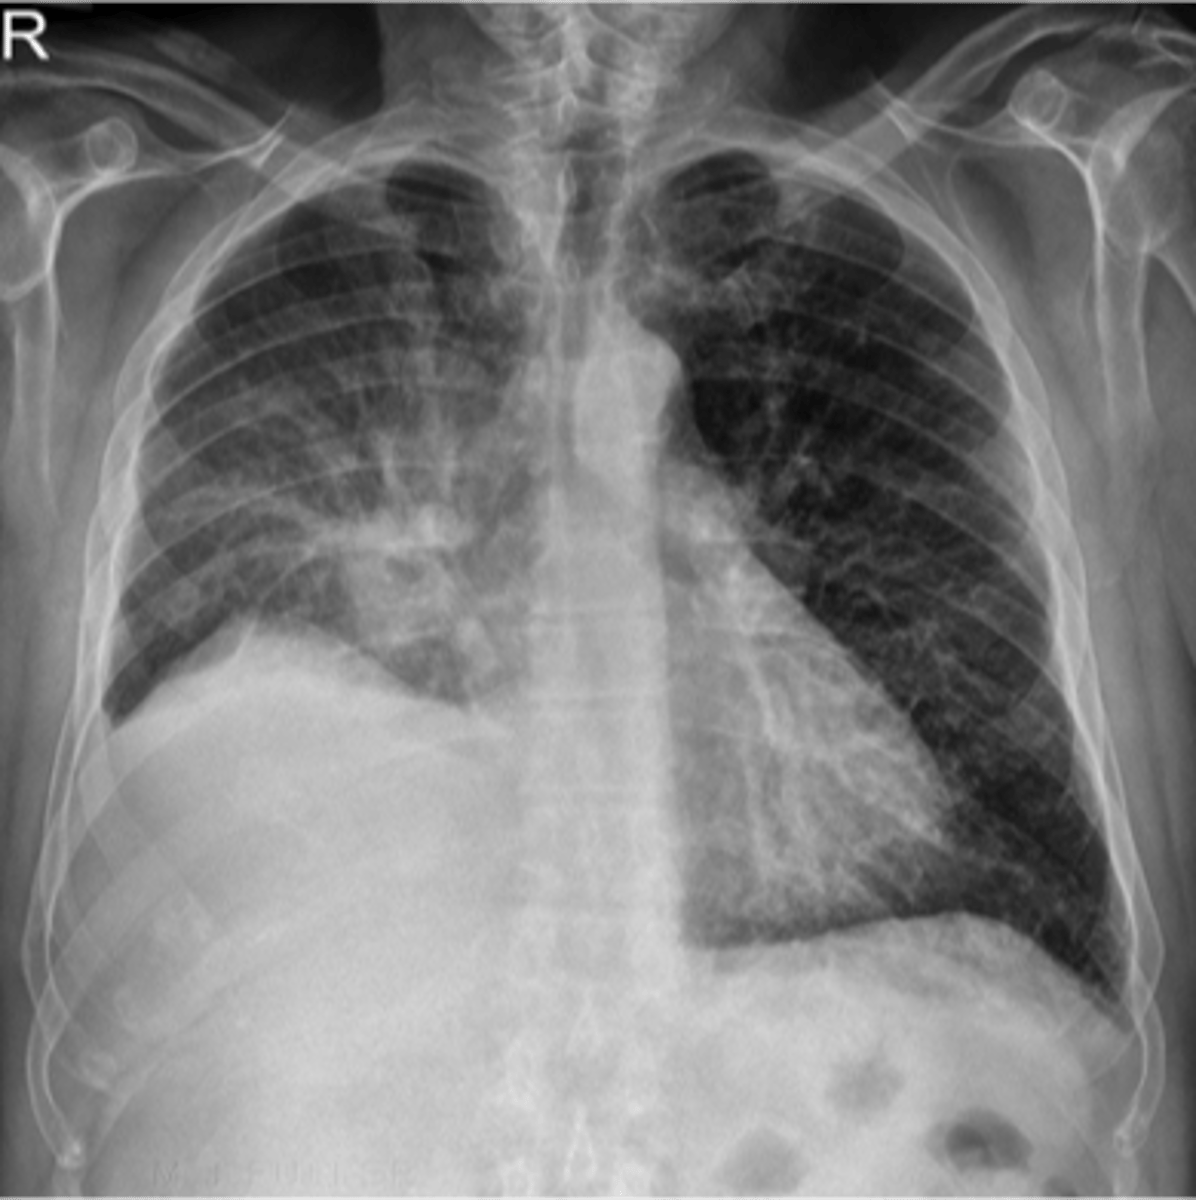

Bilateral interstitial infiltrates

air bronchogram- alveolar consolidation LUL